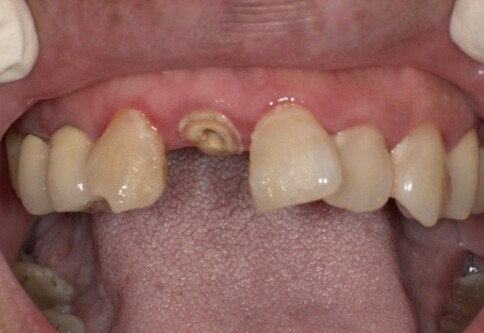

當您只有「單顆」門牙受損時,挑戰在於模仿隔壁那顆「天生的牙」。我們利用全瓷冠的高透光性創造視覺平衡,避免做出一顆看起來很新卻很突兀的假牙。

Case 3:側門齒缺牙空間調整,創造和諧外觀。